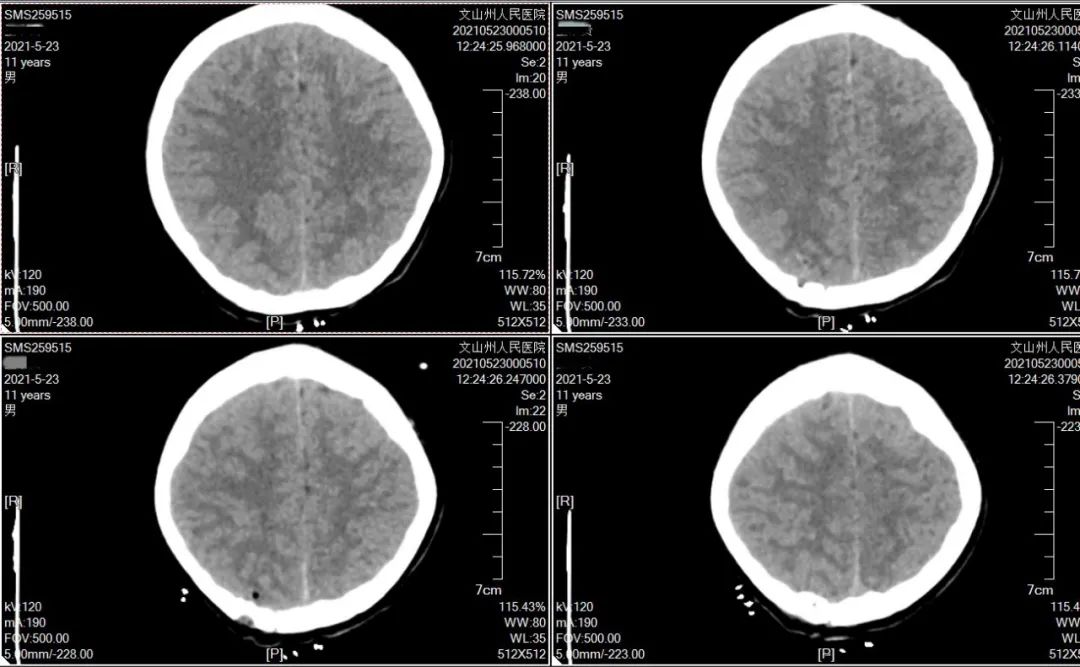

与21岁大脑比较,脑沟增宽,大脑外侧裂增宽.